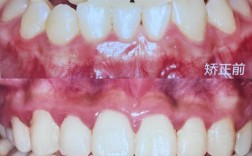

| 中部1/3区域 | 视觉核心+辅助信息 | 左侧放牙齿矫正前后对比图/隐形矫正器实物图,右侧配活动细则(如“学生凭学生证享8折”“隐形矫正赠3次洗牙”) |